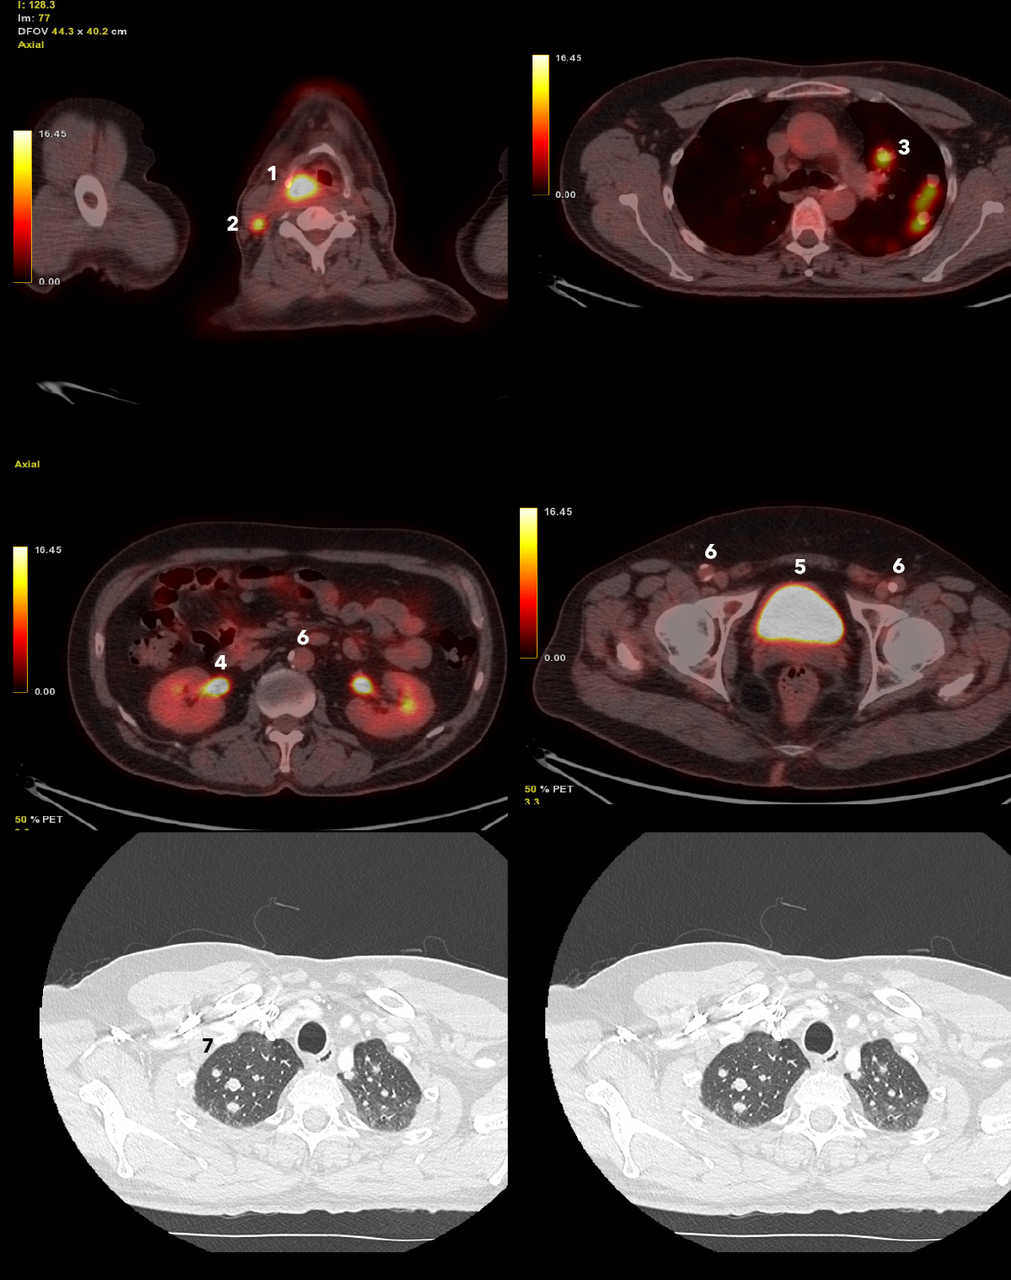

Vous recevez les examens d’imagerie suivants :

Question 8 : Vous visualisez

Hypermétabolisme physiologique (excrétion du marqueur radioactif)

Idem

Calcifications de l’aorte abdominale et des artères fémorales

TEP-scan au 18-FDG avec coupes de scanner thoracique en fenêtre parenchymateuse..

1 : hypermétabolisme pathologique, tumeur de l’hypopharynx droit ;

2 : hypemétabolisme pathologique, adénomagalie tumorale ;

3 : nodule pulmonaire hypermétabolique ;

4 : uretère : hypermétabolisme physiologique, excrétion urinaire du traceur (18-FDG) ;

5 : vessie : hypermétabolisme physiologique, excrétion urinaire du traceur (18-FDG) ;

6 : plaque d’athérome calcifiée ;

7 : nodule pulmonaire

L’examen anatomopathologique de la tumeur de l’hypopharynx droit conclut à un carcinome épidermoïde infiltrant peu différencié non kératinisant.

À propos des nodules pulmonaires, deux hypothèses semblent licites. La première est celle d’un primitif bronchique, l’autre est celle de métastases pulmonaires.